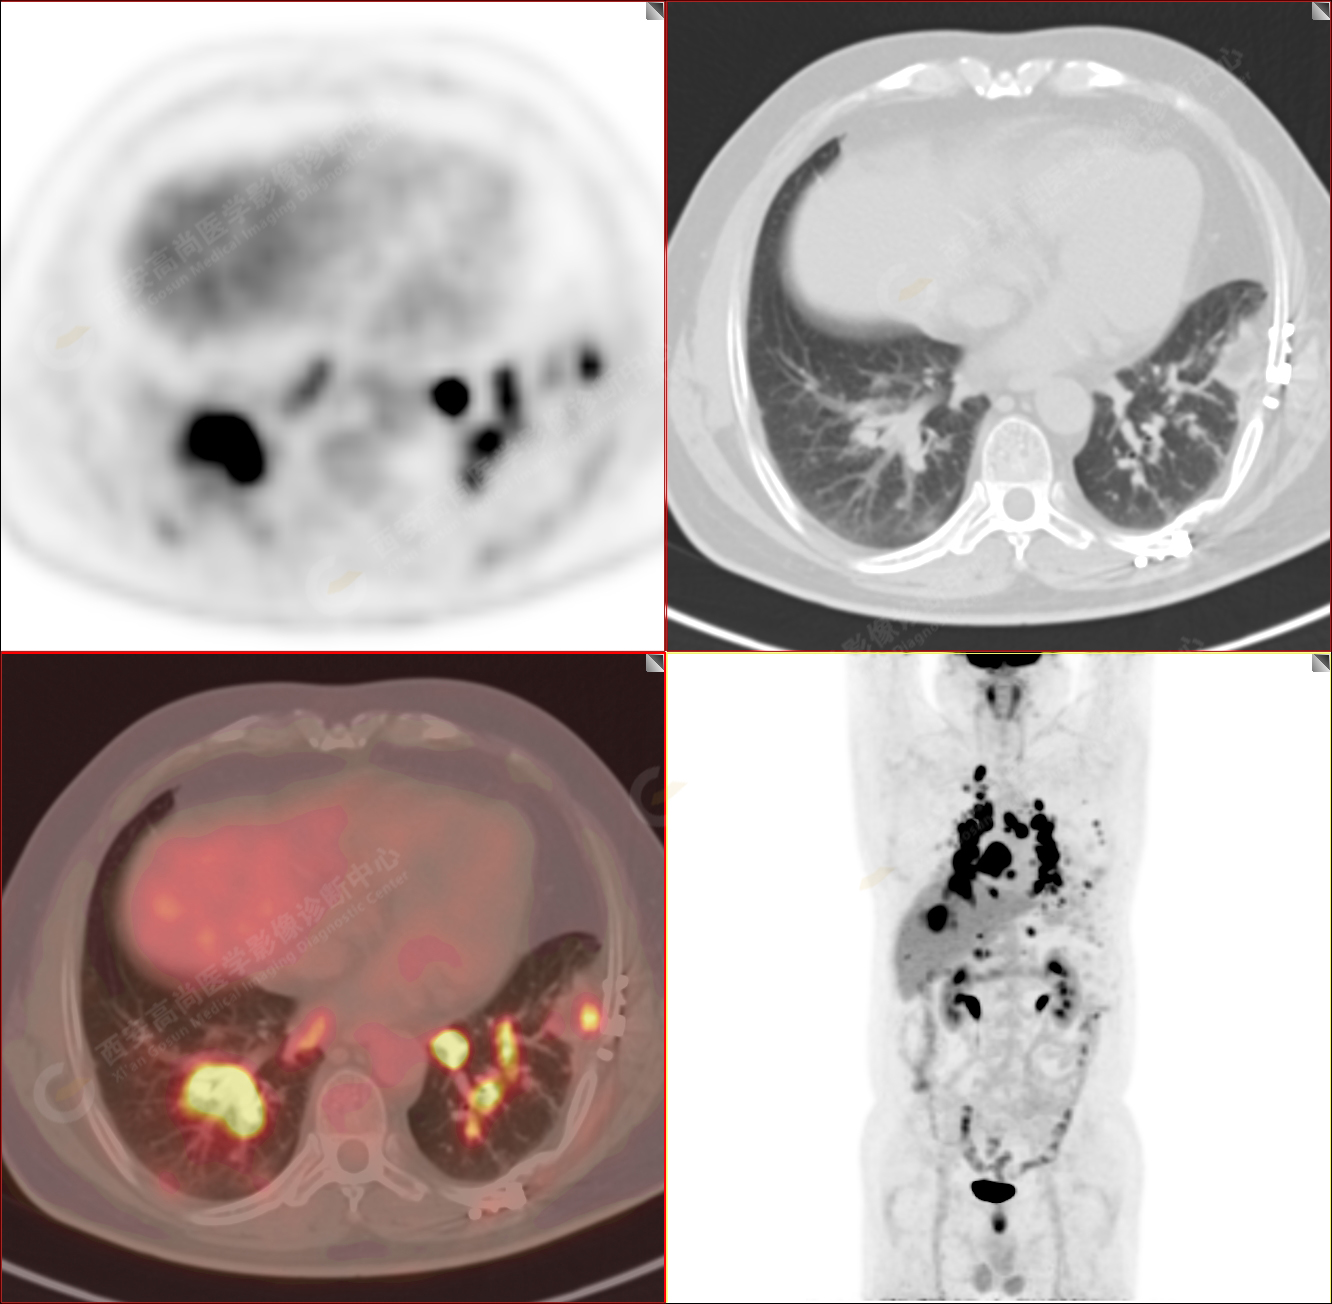

PET/CT圖像